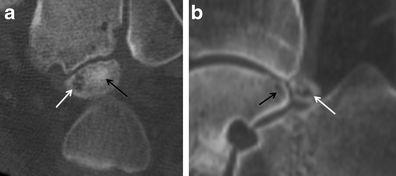

Degeneration at a synchondrosis. a Long-axis axial CT image shows increased sclerosis (black arrow) and subchondral cyst formation in an os trigonum. b Sagittal CT image reveals subchondral cyst formation in the talus (black arrow) and os trigonum (white arrow) across the synchondrosis, due to degenerative change